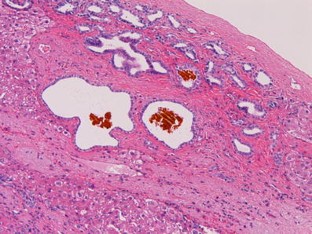

We herein report a case of monolobar hepatobiliary fibropolycystic disease. A 75-year-old woman presented with heartburn. Imaging modalities including US, CT, and MRI revealed marked atrophy and multiple biliary cysts of the hepatic left lobe. The hepatic right lobe was normal. ERCP and bile duct endoscopy revealed anomalous pancreaticobiliary union, choledochal dilation, dilation of left intrahepatic bile ducts, and small choledochal non-invasive adenocarcinoma. Polycystic kidney diseases were absent. The patient underwent pancreatico-duodenectomy and extended hepatic left lobectomy. Grossly, the hepatic left lobe was markedly atrophic, and studded with numerous biliary cysts. The left intrahepatic bile ducts were dilated (Caroli’s disease) and the common bile duct showed type I choledochal dilation. The right hepatic lobe was normal. Histologically, the hepatic left lobe was replaced by fibroelastosis. The intrahepatic bile ducts showed ductal plate malformation such as irregular contours, invaginations, and protrusions. The numerous biliary cysts also showed ductal plate malformation. There were numerous persistent ductal plates and microhamartomas. Many hyalinized destructive biliary cysts and ductal plates were recognized. The liver parenchyma was scant and free of hepatocellular malformations. The portal veins showed old obliterative portal thrombosis. The right hepatic lobe was normal. Immunohistochemically, the biliary cells were positive for cytokeratin 7, 8, 18 and 19, and MUC6 and CD10, but negative for MUC2 and MUC5AC. The biliary cysts, persistent ductal plate, and microhamartomas were positive for fetal apomucin antigen MUC1.

Fig. 4